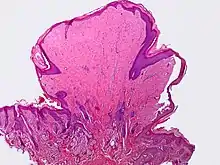

Tumor vaginal Benigno Referencias Tumor Yolk sac no [16][17][18][19][20][21][22] Tumor neuroectodérmico primitivo Periferal no [16][17][18][23] Melanoma vaginal no [16][17][18][24][25] Blue nevus sí[26] [16][17][18][25] Carcinosarcoma no [18] Sarcoma botryoides no [9][16][17][18][22][27][28] Leimiosarcoma no [18][29] Sarcoma Endometrioide estromal no [18][30] Sarcoma vaginal no diferenciado [18] Leiomioma sí [6][13][16][17][18] Genital rhabdomyoma [16][17][18][31][32][33] Deep angiomyoxoma [16][17][18] Spindle cell nodule [9][16][17][18][34] Carcinoma no diferenciado [16][17][18] Carcinoma de células pequeñas no [16][17][18] Carcinoide no [18] Carcinoma Adenoide basal [18] Carcinoma Adenosquamous no [18] Adenoma sí [35] Adenocarcinoma mucinoso [18] Papilloma Squamous sí [16][17][18] Adenocarcinoma de endometrio no [18] Clear cell adenocarcinoma no [16][17][18] Pólipo fibroepiteleal sí [16][17][18] Squamous intraepithelial neoplasia [16][17][18] Verruga genital sí [6][16][17][18] Carcinoma espinocelular no [16][17][18] Mesenchymal tumors [18] Alveolar soft part sarcoma [18] Mixed epithelial and mesenchymal Tumors [18] Malignant mixed Tumors resembling synovial sarcoma [18] Tumores mezclados benignos [18] Adenomatoides sí [18] Linfoma maligno no [18] Sarcoma granulocítico [18] Fibroepithelial polyp sí [6][17] Verrucous carcinoma no [9] Squamotransitional cell carcinoma [9]